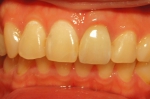

上前歯オールセラミックブリッジ

写真左側の上前歯3本がオールセラミックブリッジ。(当院で治療)

右側の上前歯2本は元から入っていたメタルセラミッククラウン。

既存の歯と同じシェード(規格の色)ですがオールセラミックは金属の土台が透けないのでより白味や透明感がきれいに出ます。